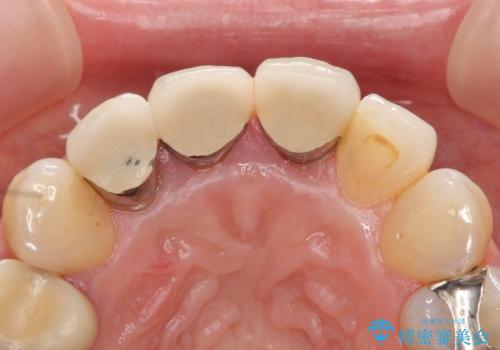

- 前歯の長さが違うのが気になるといらっしゃった方の症例です。

根尖病変を認めたため再根管治療を行った後、オールセラミッククラウン(スペシャル)にて補綴を行いました。

歯肉の腫れをより改善するため歯周外科を提案しましたが希望されませんでした。